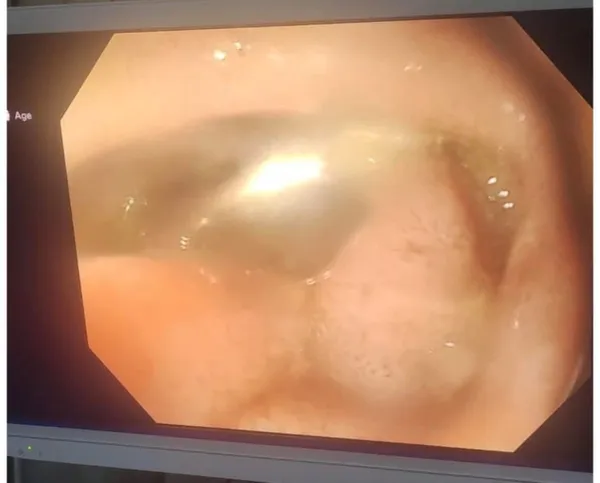

استقبل قسم الطوارئ بمركز كبد كفر الشيخ طفلًا صغيرًا بعد ابتعاله جسمًا حادًا (مسمار طويل) استقر داخل الاثنى عشر، مما تسبب في آلام شديدة بالبطن مع قيء متكرر، وكانت الحالة تستدعي تدخلاً عاجلاً، وتم تجهيز الطفل لاحتمال دخوله غرفة العمليات.

وتمكن فريق طبي بالمركز من التعامل مع الحالة بسرعة ودقة، وتم استخراج المسمار بنجاح كامل باستخدام المنظار دون الحاجة لأي تدخل جراحي، مما جنّب الطفل مخاطر الجراحة وسمح له بالخروج بحالة مستقرة وآمنة.